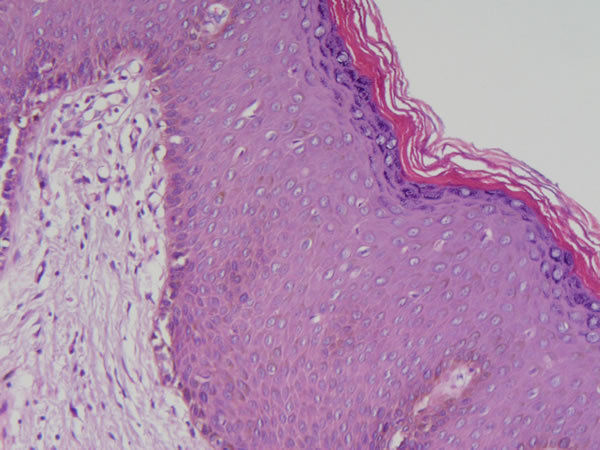

Pele - epit. pavimentoso estratificado normal |